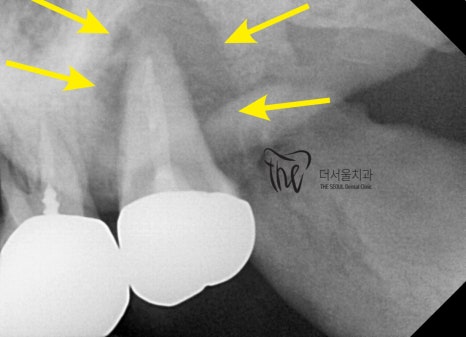

우선, 진단 내용은 사진에서 보실 수 있는 것 처럼

금니 통증 의 위치는 상악동의 위치와

긴밀해 있습니다. 거리가 꽤나 가깝죠?

이렇게, 미리

- 골질 파악

- 잇몸의 두께 파악

- 최종 보철의 형태

- 해부학적 구조물들의 위치

등을 정확하게 미리 알 수 있기 때문에